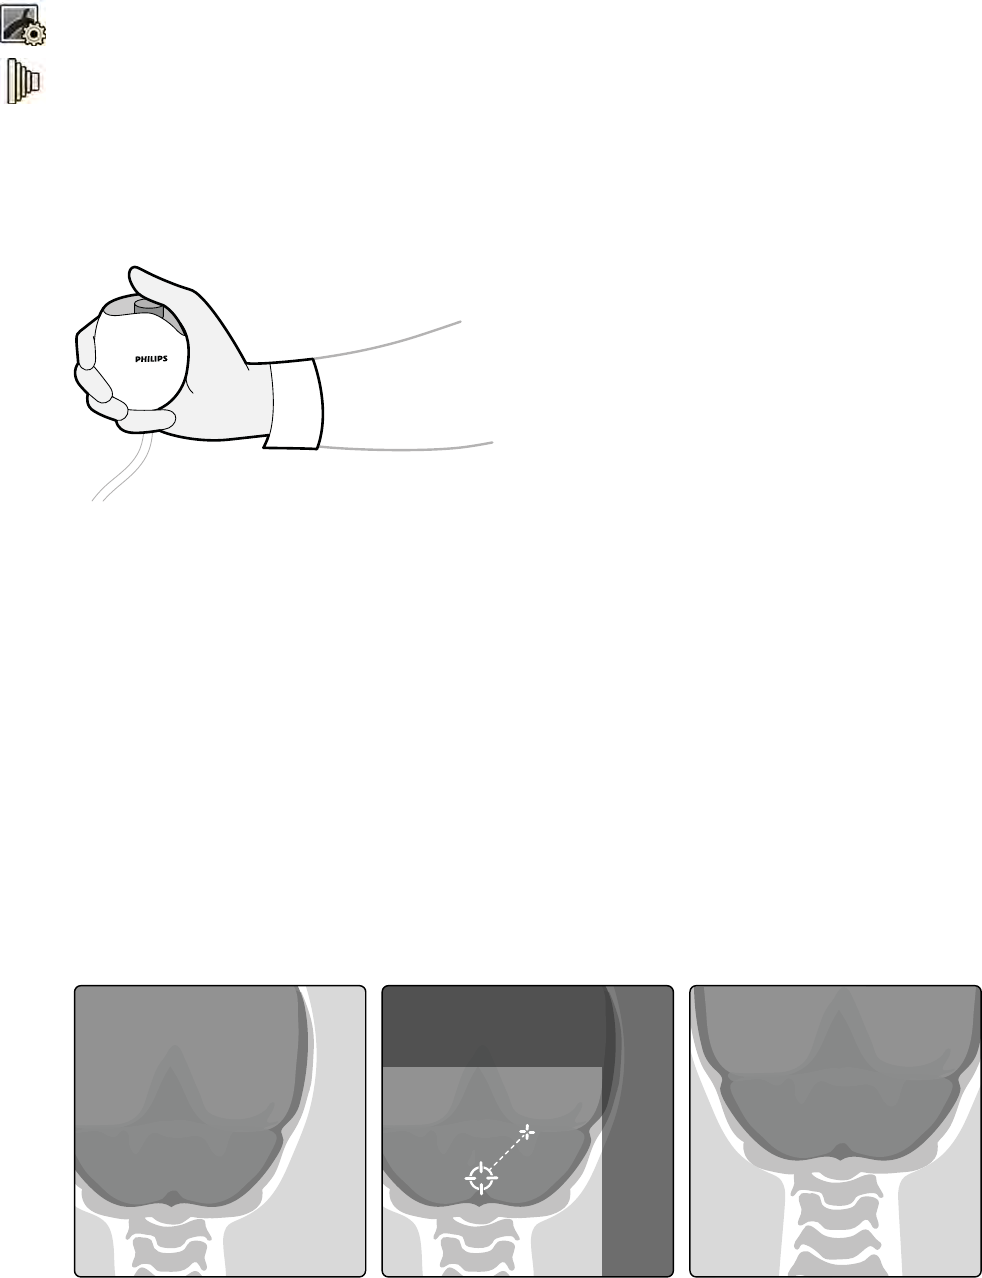

6.7 Ustawianie w izocentrum....................................................................................................... 89

6.7.1 Przywoływanie pozycji izocentrum........................................................................ 90